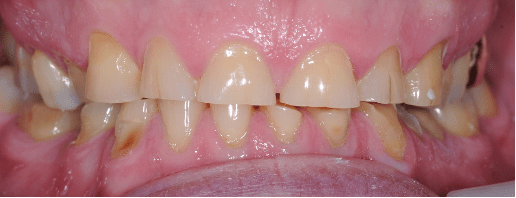

Another case of mild toothwear and discolouration was treated with direct composite bonding.